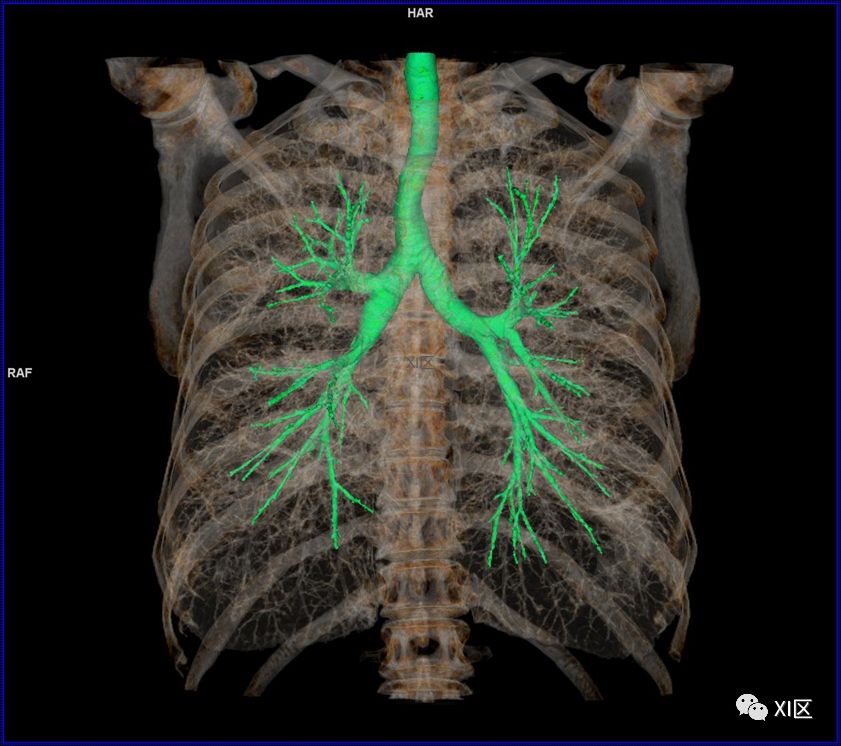

前后位,双侧位,后前位显示气道肺与胸部骨骼的关系

气管支气管树与两肺融合显示